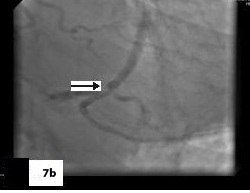

Five patients (12.5 %) had normal angiograms [Table/Fig-2,2b,3,3b], six (15%) had non-significant disease [Table/Fig-4,4b,5a,5b] and 29 patients (72.5%, 26 male & 3 female) had significant disease [Table/Fig-6a,6b],[7a,7band8] on CT coronary angiography, which was also proved on invasive angiography [Table/Fig-9]. The incidence of significant coronary detected was highest in age group of 41-60 years [Table/Fig-10].

(Sagittal), (Axial), (VRT) images & catheter angiography image showing significant stenosis in mid LAD